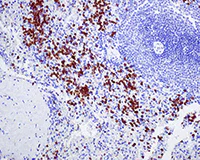

Immunohistochemistry (Formalin/PFA-fixed paraffin-embedded sections) - Anti-NOXA2/p67phox antibody [EPR5064] - BSA and Azide free (AB239969)

Immunohistochemical analysis of NOXA2/p67phox in paraffin-embedded Human spleen tissue using ab109366 at 1/500 dilution

This data was developed using the same antibody clone in a different buffer formulation containing PBS, BSA, glycerol, and sodium azide (ab109366).

Perform heat mediated antigen retrieval with citrate buffer pH 6 before commencing with IHC staining protocol.